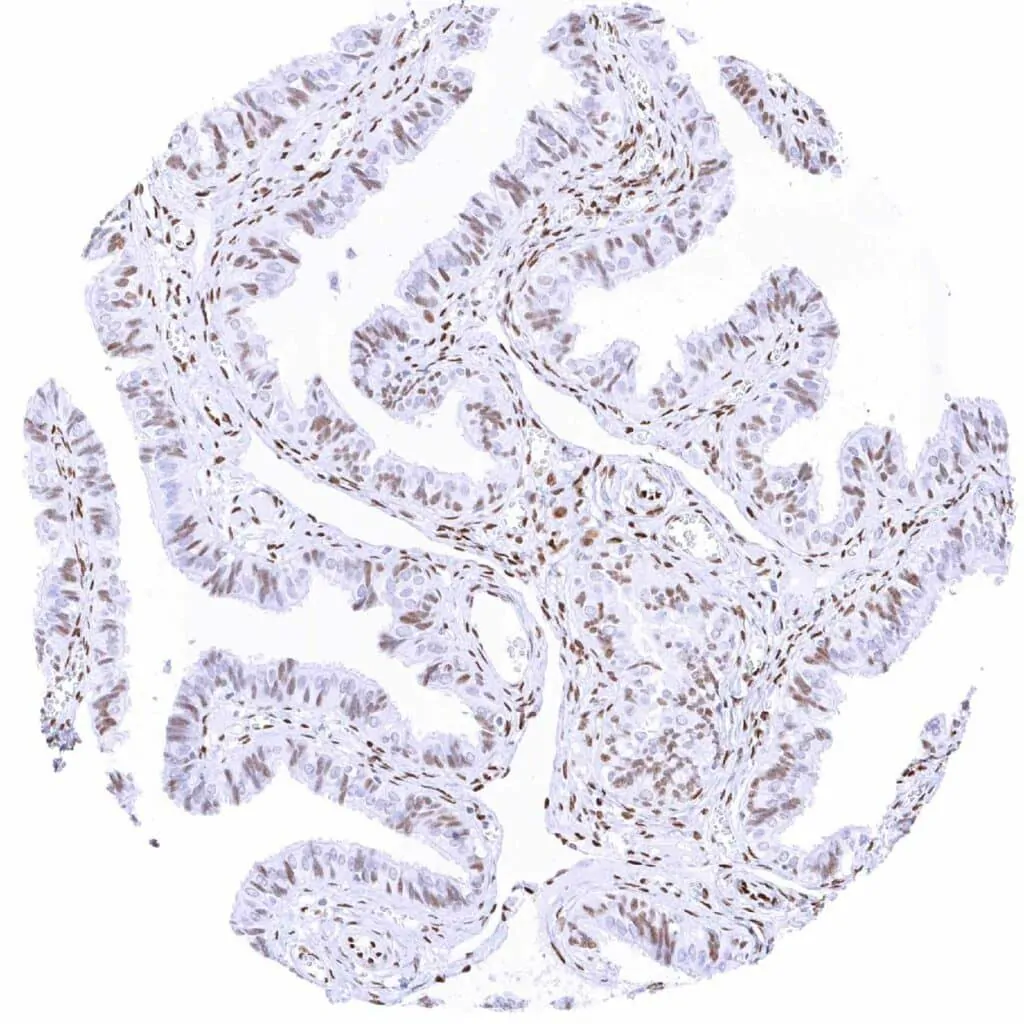

Uterus, endometrium (proliferation) – Moderate to strong TLE1 staining of epithelial and stromal cells